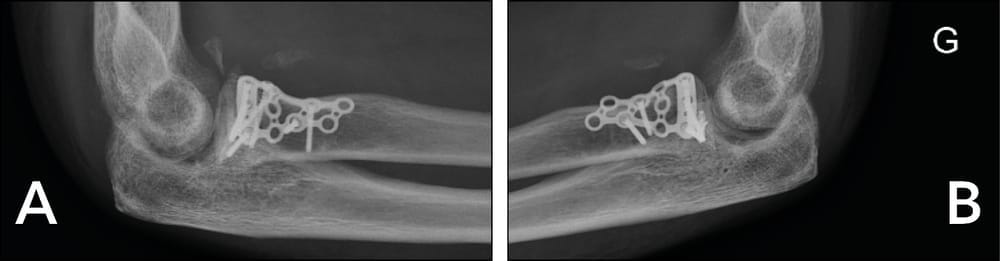

ORIF of the radial head seems to be accessible from the left side. After exposure, reconstruction proves not to be possible. A capitellum graft is harvested and fracture repair is achieved through a Medartis plate (Figure 4).

Ablation of the hardware between 12 and 18 months later. Radiological assessment shows consolidation and integration of the graft (Figure 5).

At the most recent follow-up after 2 years, the ranges of motion in flexion–extension were 0/20/135 on the right and left, with full and symmetrical pronation and supination. However, the Jamar dynamometer assessment showed a deficiency in strength, with 6 kg on the right wrist and 2 kg on the left, related to ulnar neuropathy, and overall the functional outcome was poor and had led to post-traumatic depression.